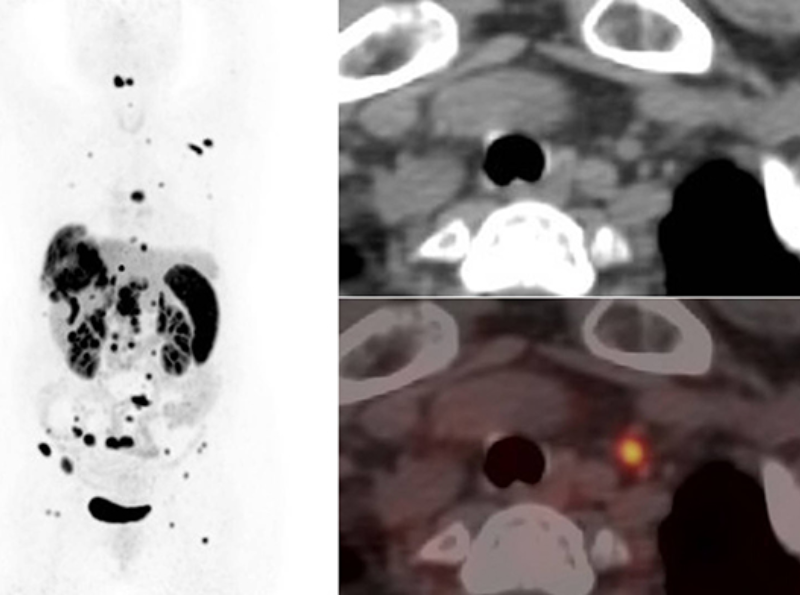

Small Lesions Detectability with Gallium-68

The large 30 cm axial digital PET field of view (FOV) with 2.9 mm NEMA resolution and the 160-slice CT with 0.25 mm isotropic spatial resolution improves quantitative accuracy and small lesion detectability.